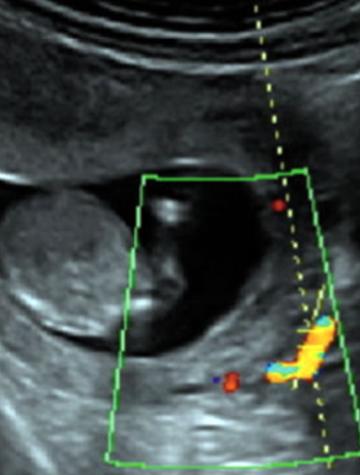

Le dépistage précoce de la prééclampsie perme8rait de mieux stra7fier le niveau de risque vasculaire des pa7entes afin de choisir le type de suivi de la grossesse. Actuellement, on s’oriente vers un dépistage combiné fondé sur des facteurs de risques cliniques, sur le Doppler utérin et sur des marqueurs biologiques.